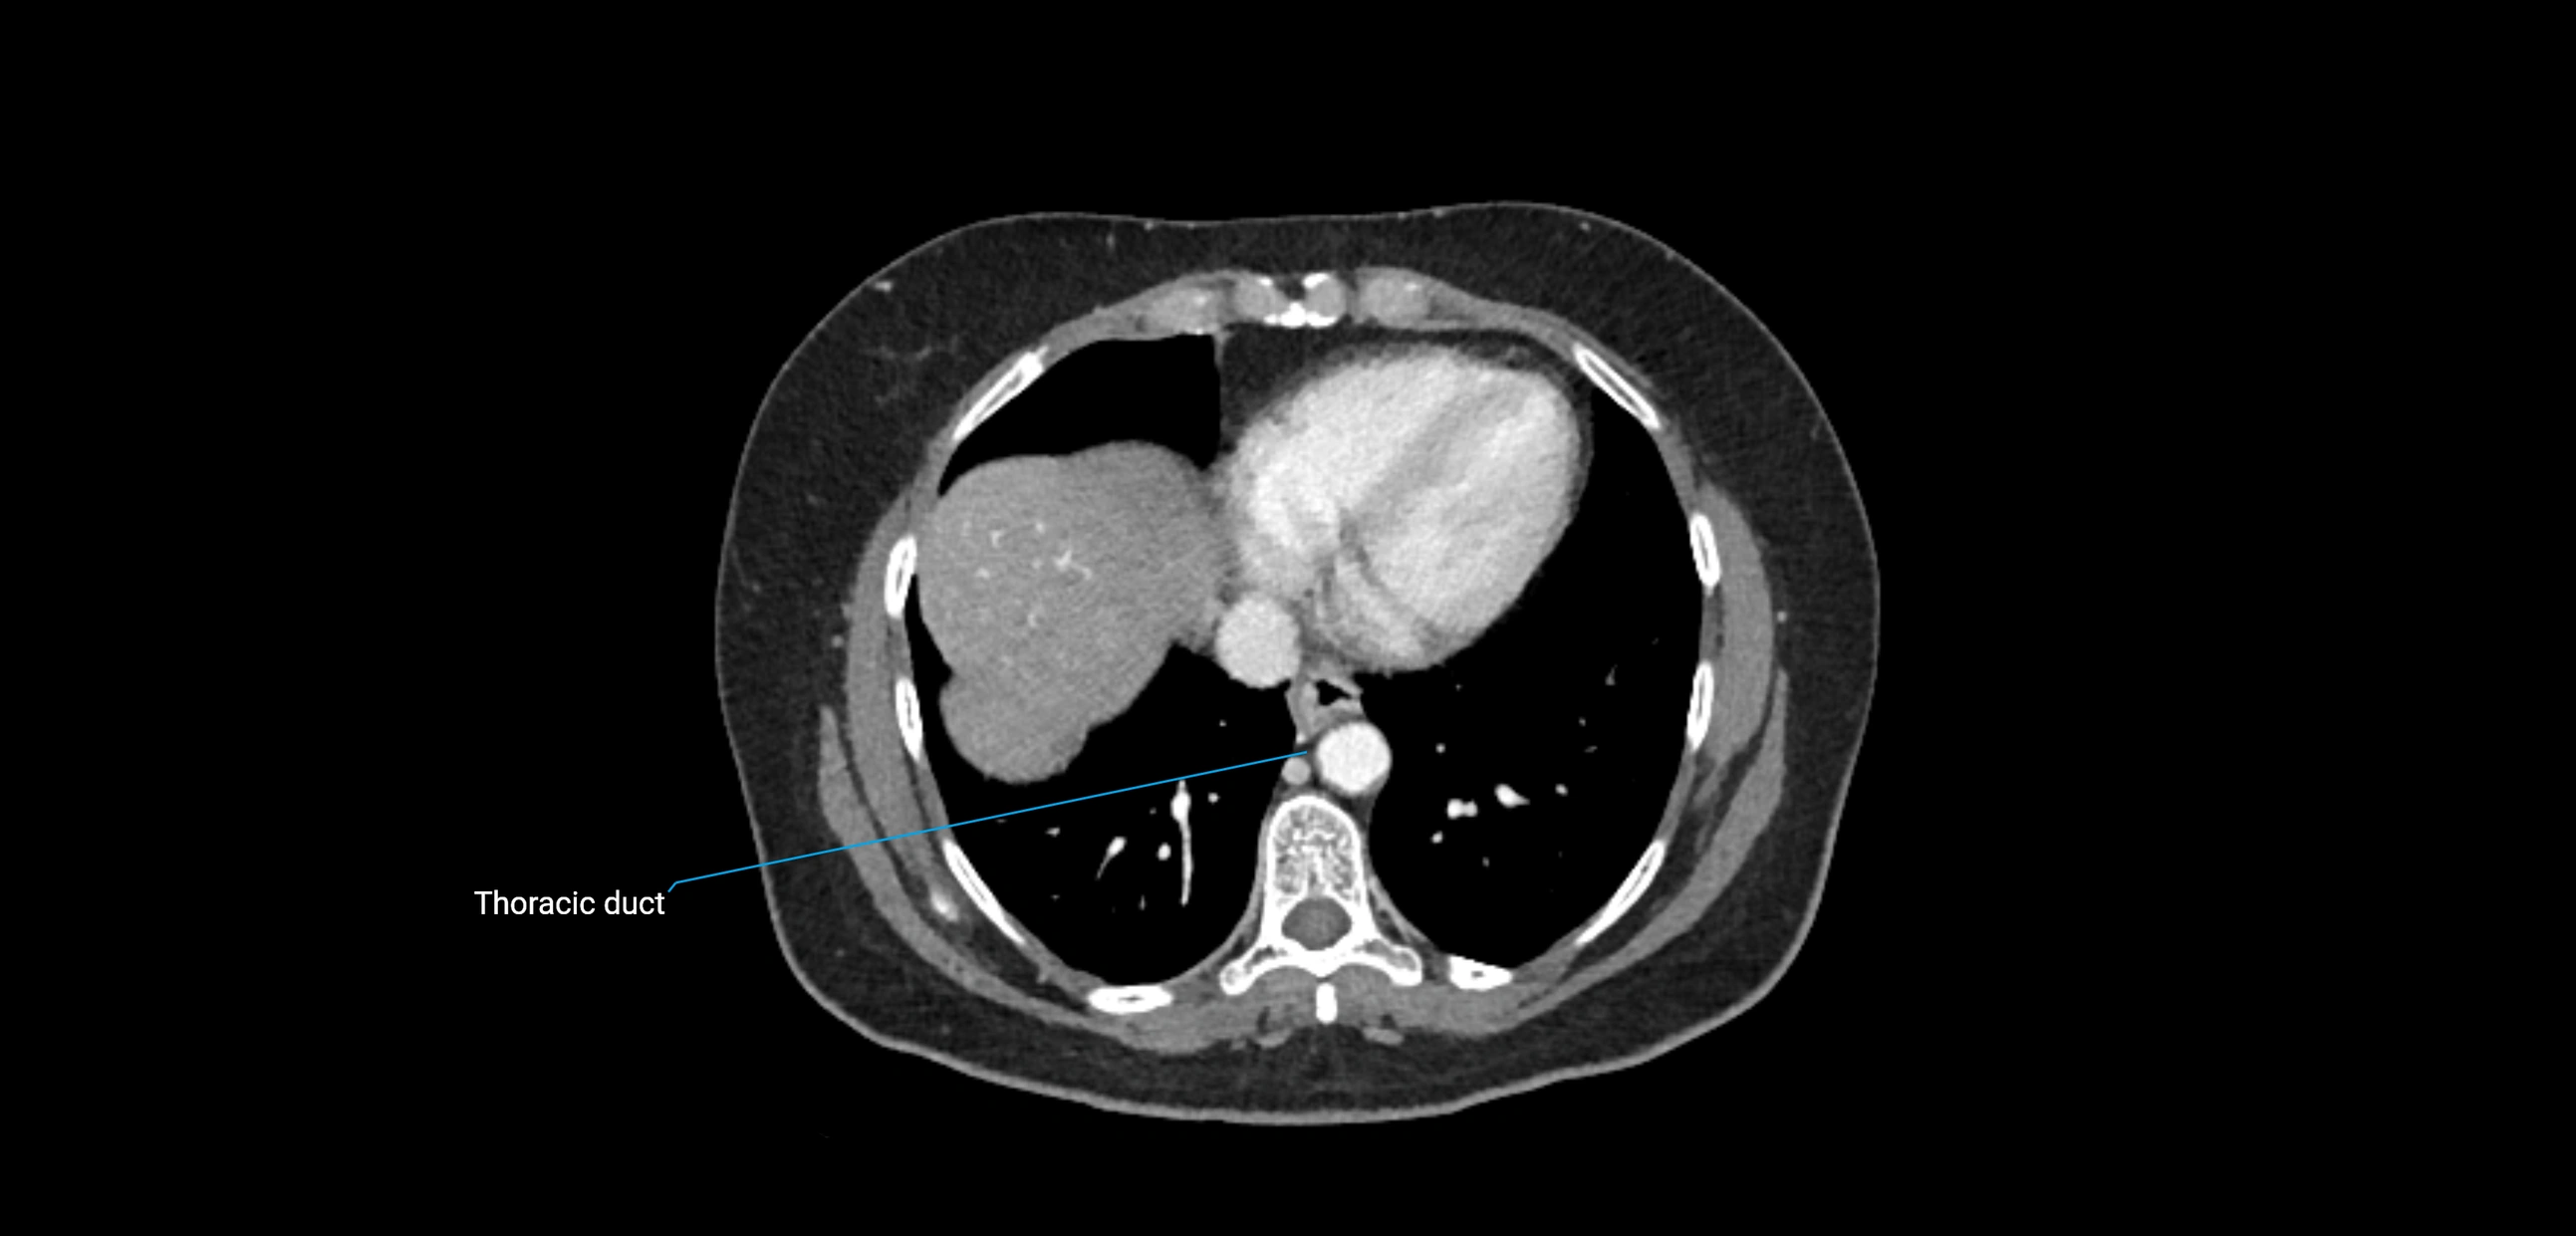

CT image

image